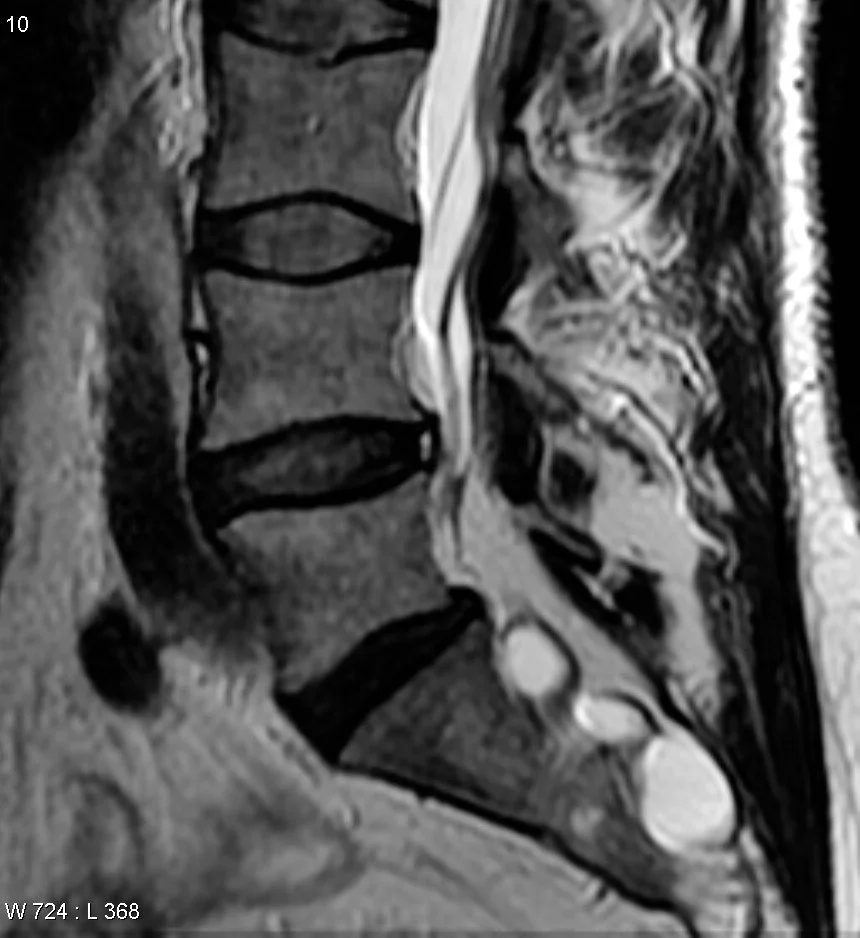

Tarlov Cyst (Perineural Cyst)

• CSF filled dilation of nerve root sheath (basically CSF filled cyst)

• Extra-dural (but do contain neural tissue)

• Associated with connective tissue disease (marfans, Ehlers danlos, etc)

• Typically asymptomatic, may cause mass effect causing related symptoms to whatever they compress

• Findings

• Will follow CSF characteristics

• T1: low signal

• T2: high signal

• T1 C+: does not enhance